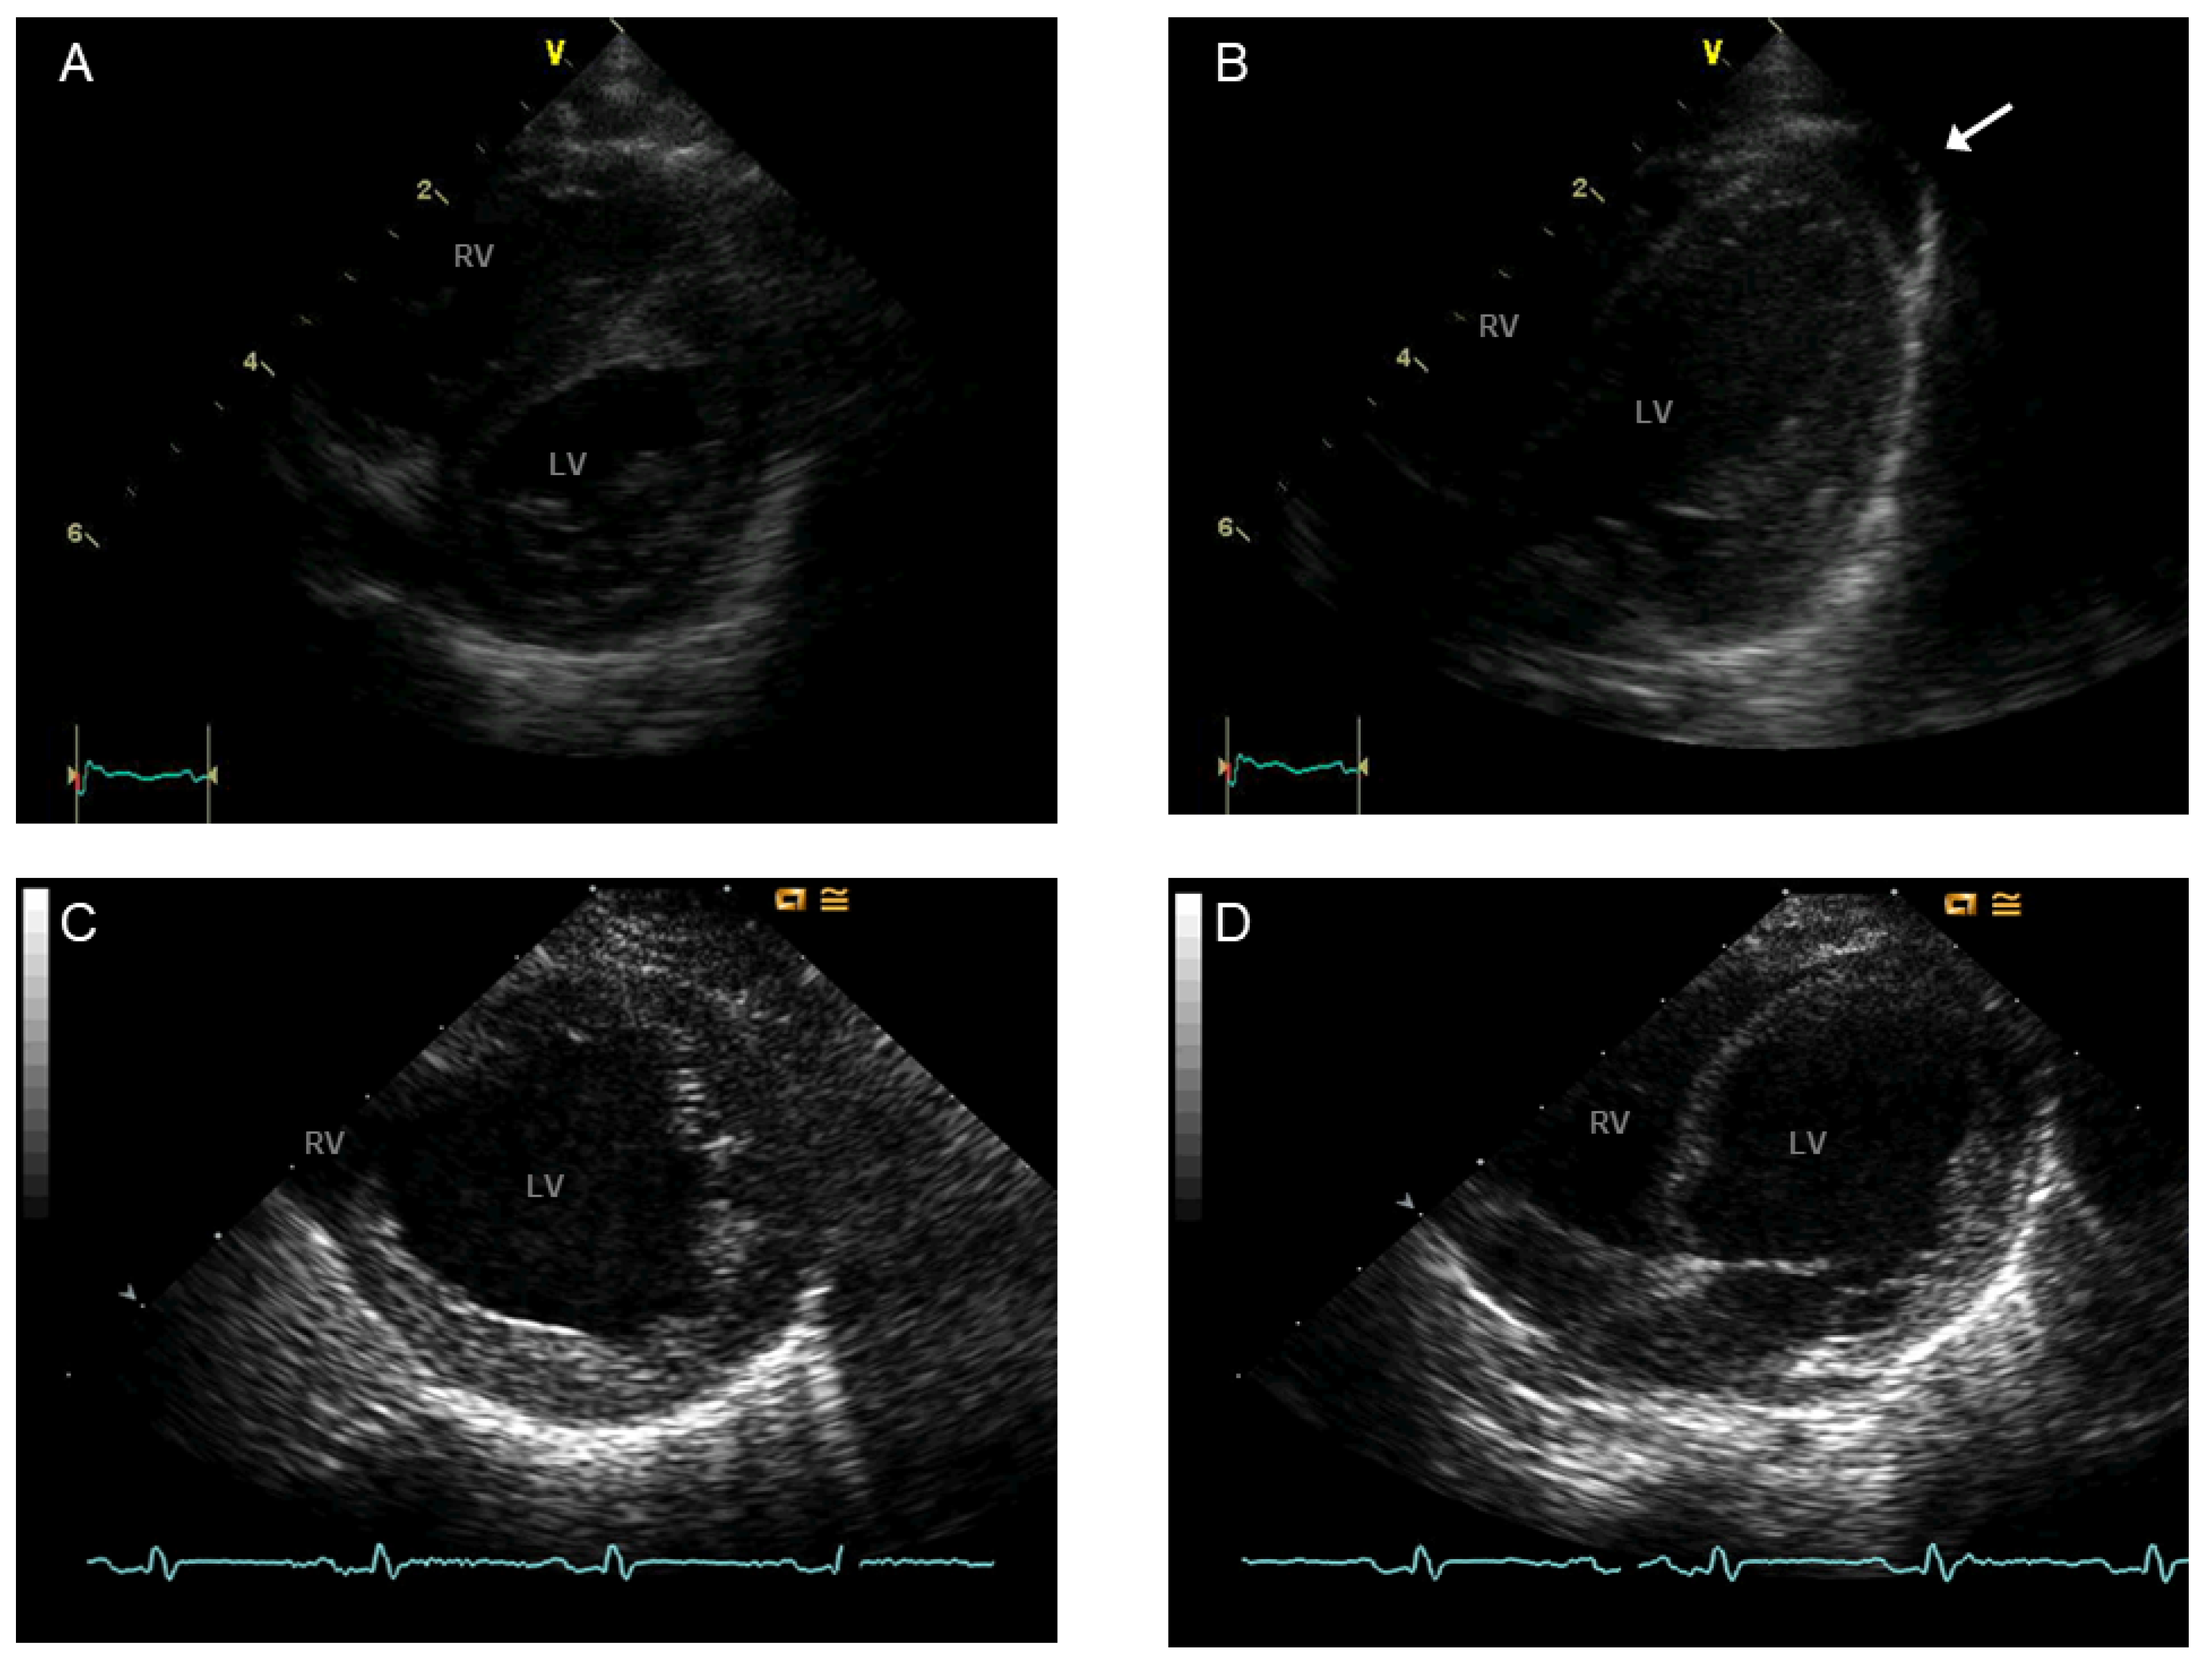

- Villalba-Orero, M.; Lopez-Olaneta, M.M.; Gonzalez-Lopez, E.; Padron-Barthe, L.; Gomez-Salinero, J.M.; Garcia-Prieto, J.; Wai, T.; Garcia-Pavia, P.; Ibanez, B.; Jimenez-Borreguero, L.J.; et al. Lung ultrasound as a translational approach for non-invasive assessment of heart failure with reduced or preserved ejection fraction in mice. Cardiovasc. Res. 2017, 113, 1113–1123. [Google Scholar] [CrossRef]